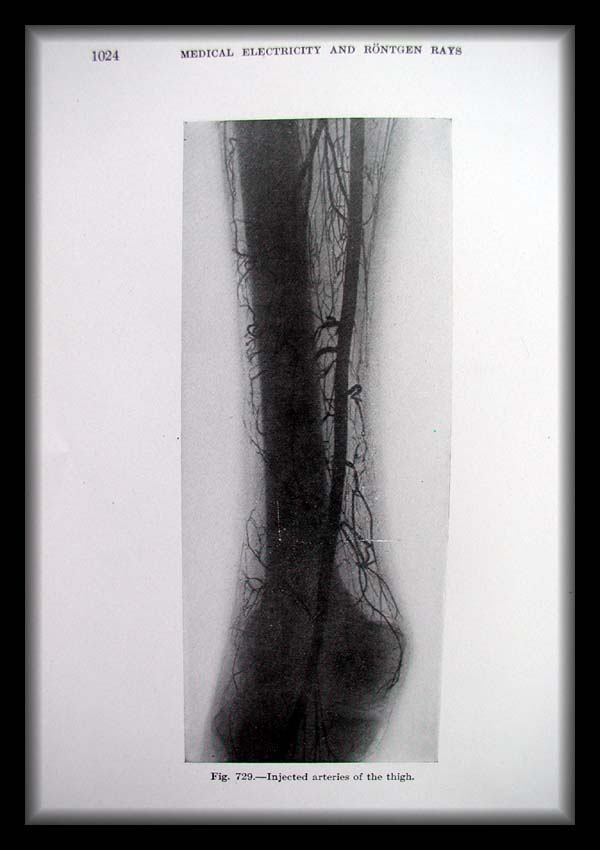

Page1024